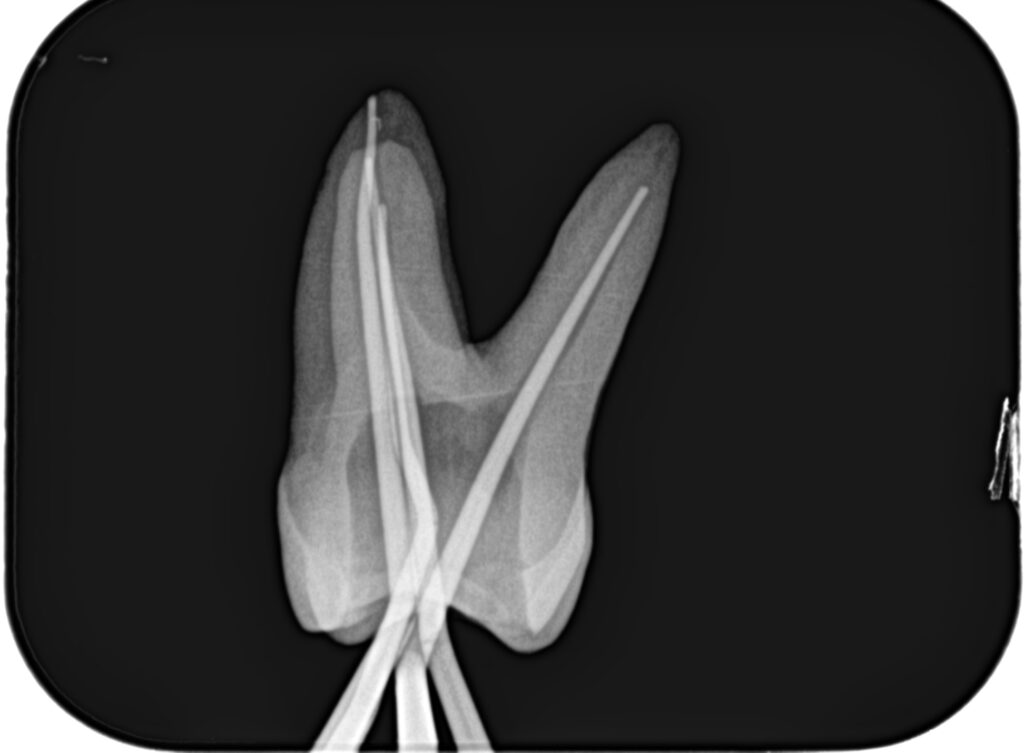

まず作業長の測定方法を行うまでを解説した。

その後、根管形成である。

上記動画では、細い穿通させた根管を号数を下げずにWave One Gold #25だけで作業長まで形成している。

根管形成が終了すれば、根管充填だ。

日曜日は実習を行った。

土曜日の内容を投影した実習であった。

2本の歯牙で実習し、あっという間に1日は終了した。